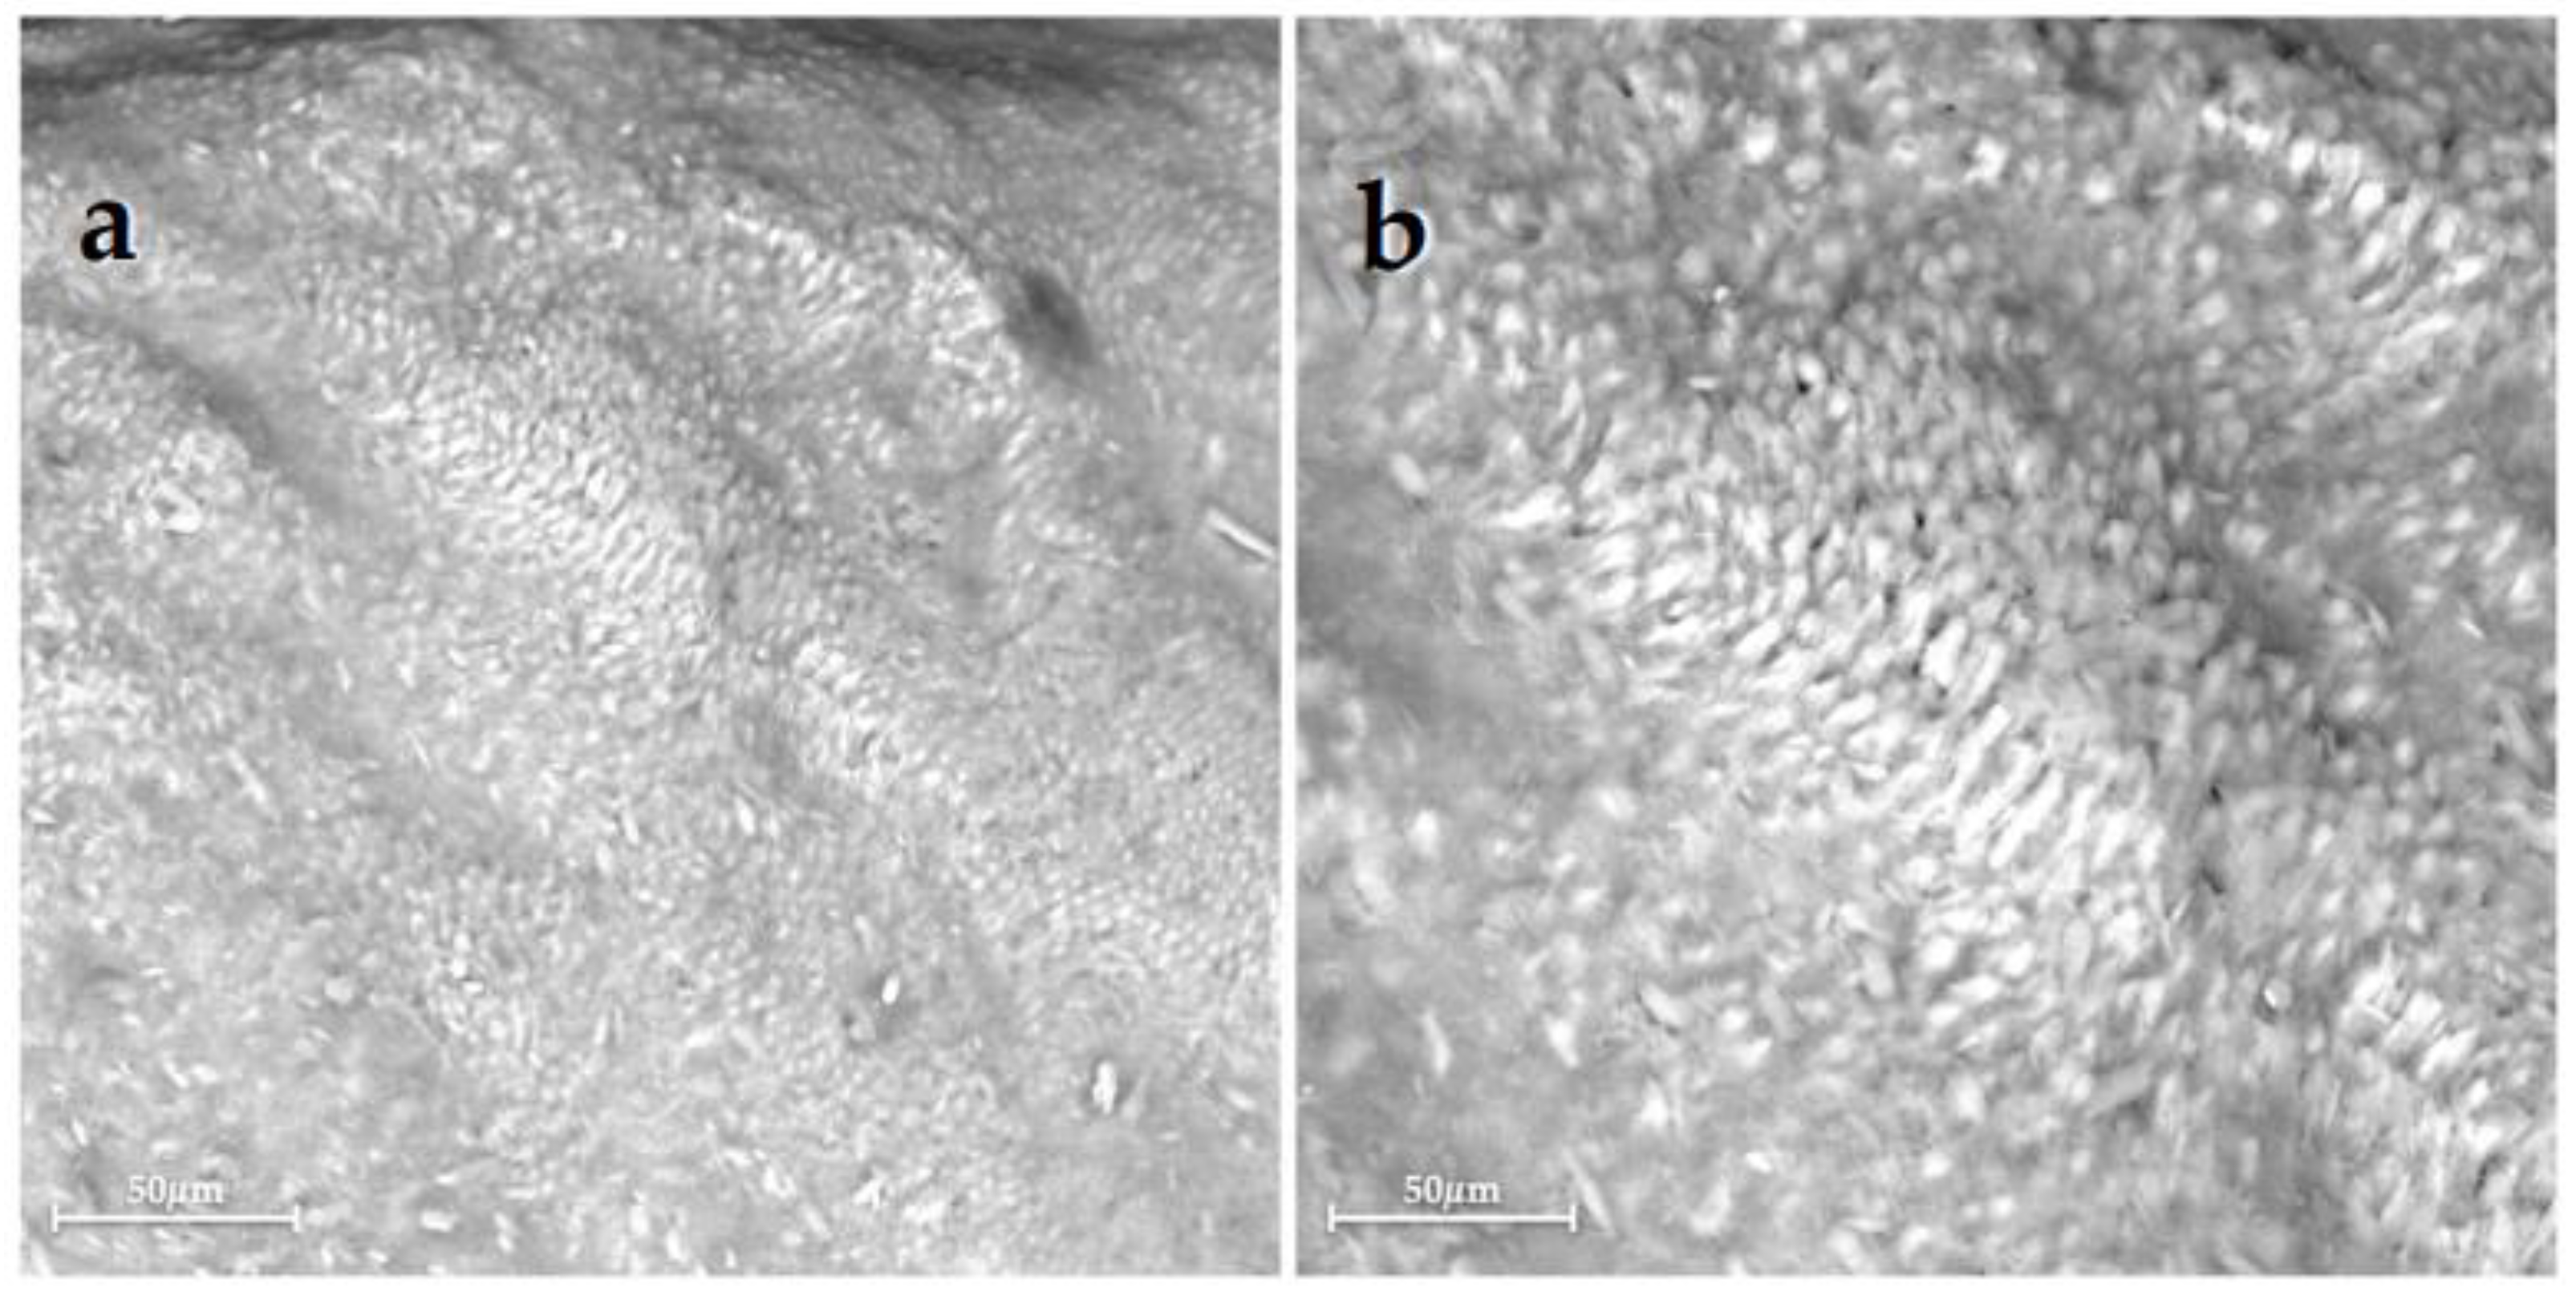

Figure 1 and Figure 2 show scanning electron micrographs of each group (1–6), which display different enamel surface morphologies.

Scanning electron micrographs of Group 1, sound enamel without any treatment, showed the typical aspect of the intact enamel crystalline organization (Figure 1). Differently, Group 2, the demineralized untreated enamel, presented extensive surface alterations with a large dissolution of interprismatic area due to the demineralization process (Figure 2).

SEM results of Group 1, which was not treated, depict healthy enamel, homogeneously exhibiting HA crystals integrity with organized rods (Figure 1). On the contrary, Group 2 confirmed that the demineralization process led to enamel alterations with many exposed enamel prisms, depressions, and irregularities, the destruction of interprismatic spaces, and the loss of interprismatic substances, typical of enamel’s demineralization morphology (Figure 2). However, these morphological changes of the tooth surface, at the early stage, are reversible and can be repaired by the application of RA. The rationale supporting the use of these RA is their efficacy in the remineralization of early carious lesions, advocating a mini-invasive and preventive approach rather than the traditional invasive clinical ones. Indeed, the EDX results of the treated enamel of Groups 3–6 showed an increase in remineralization compared with Group 2 (p < 0.05). However, since Group 3 highlighted a quite high variability in results, these data should be interpreted with caution.

Figure 1. Scanning electron micrographs of the Group 1 displayed (a) at 500× magnification, showing the typical morphology of sound enamel with emphasized perikymatas; and (b) at 1000× magnification, showing slight erosion of the enamel surface.